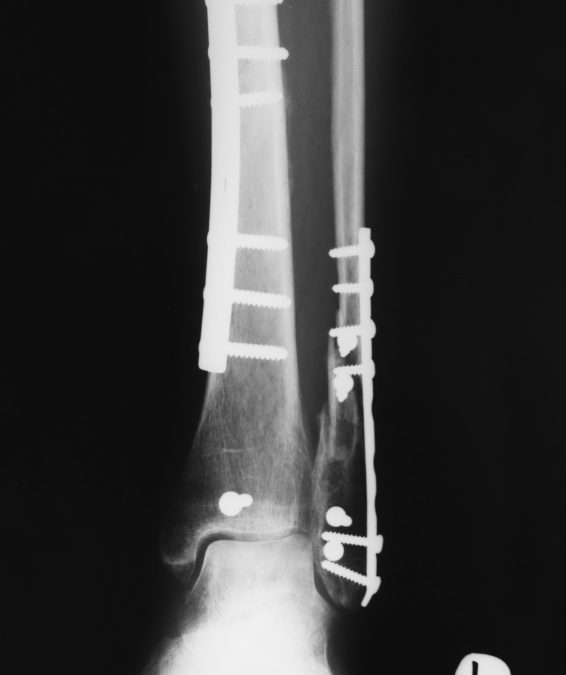

Tid Bits of Info If you twist your ankle badly and cannot walk on it due to pain, seek medical help. Treat all acute injuries with the RICE (Rest, Ice, Compression, Elevation) principles of acute injury management. Normal healing time of most bone fractures...